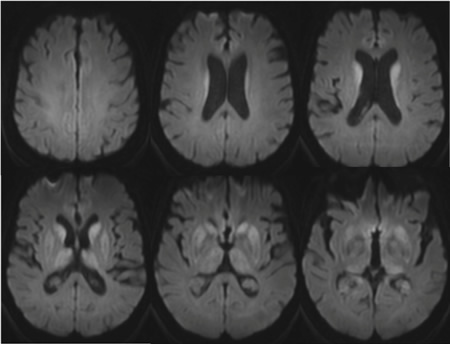

As primeiras 5 imagens são imagens FLAIR (recuperação da inversão atenuada por fluidos) de paciente com meningoencefalite por vírus da varicela-zóster exibindo hiperintensidades de substância cinzenta e branca. A última imagem é a imagem T1 com contraste exibindo captação difusa no parênquima e na leptomeninge

Do acervo pessoal de Eric E. Kraus; usado com permissão